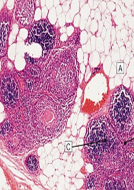

Hiperplasia patológica: hiperplasia prostática benigna. Estímulo desencadenante → andrógenos.